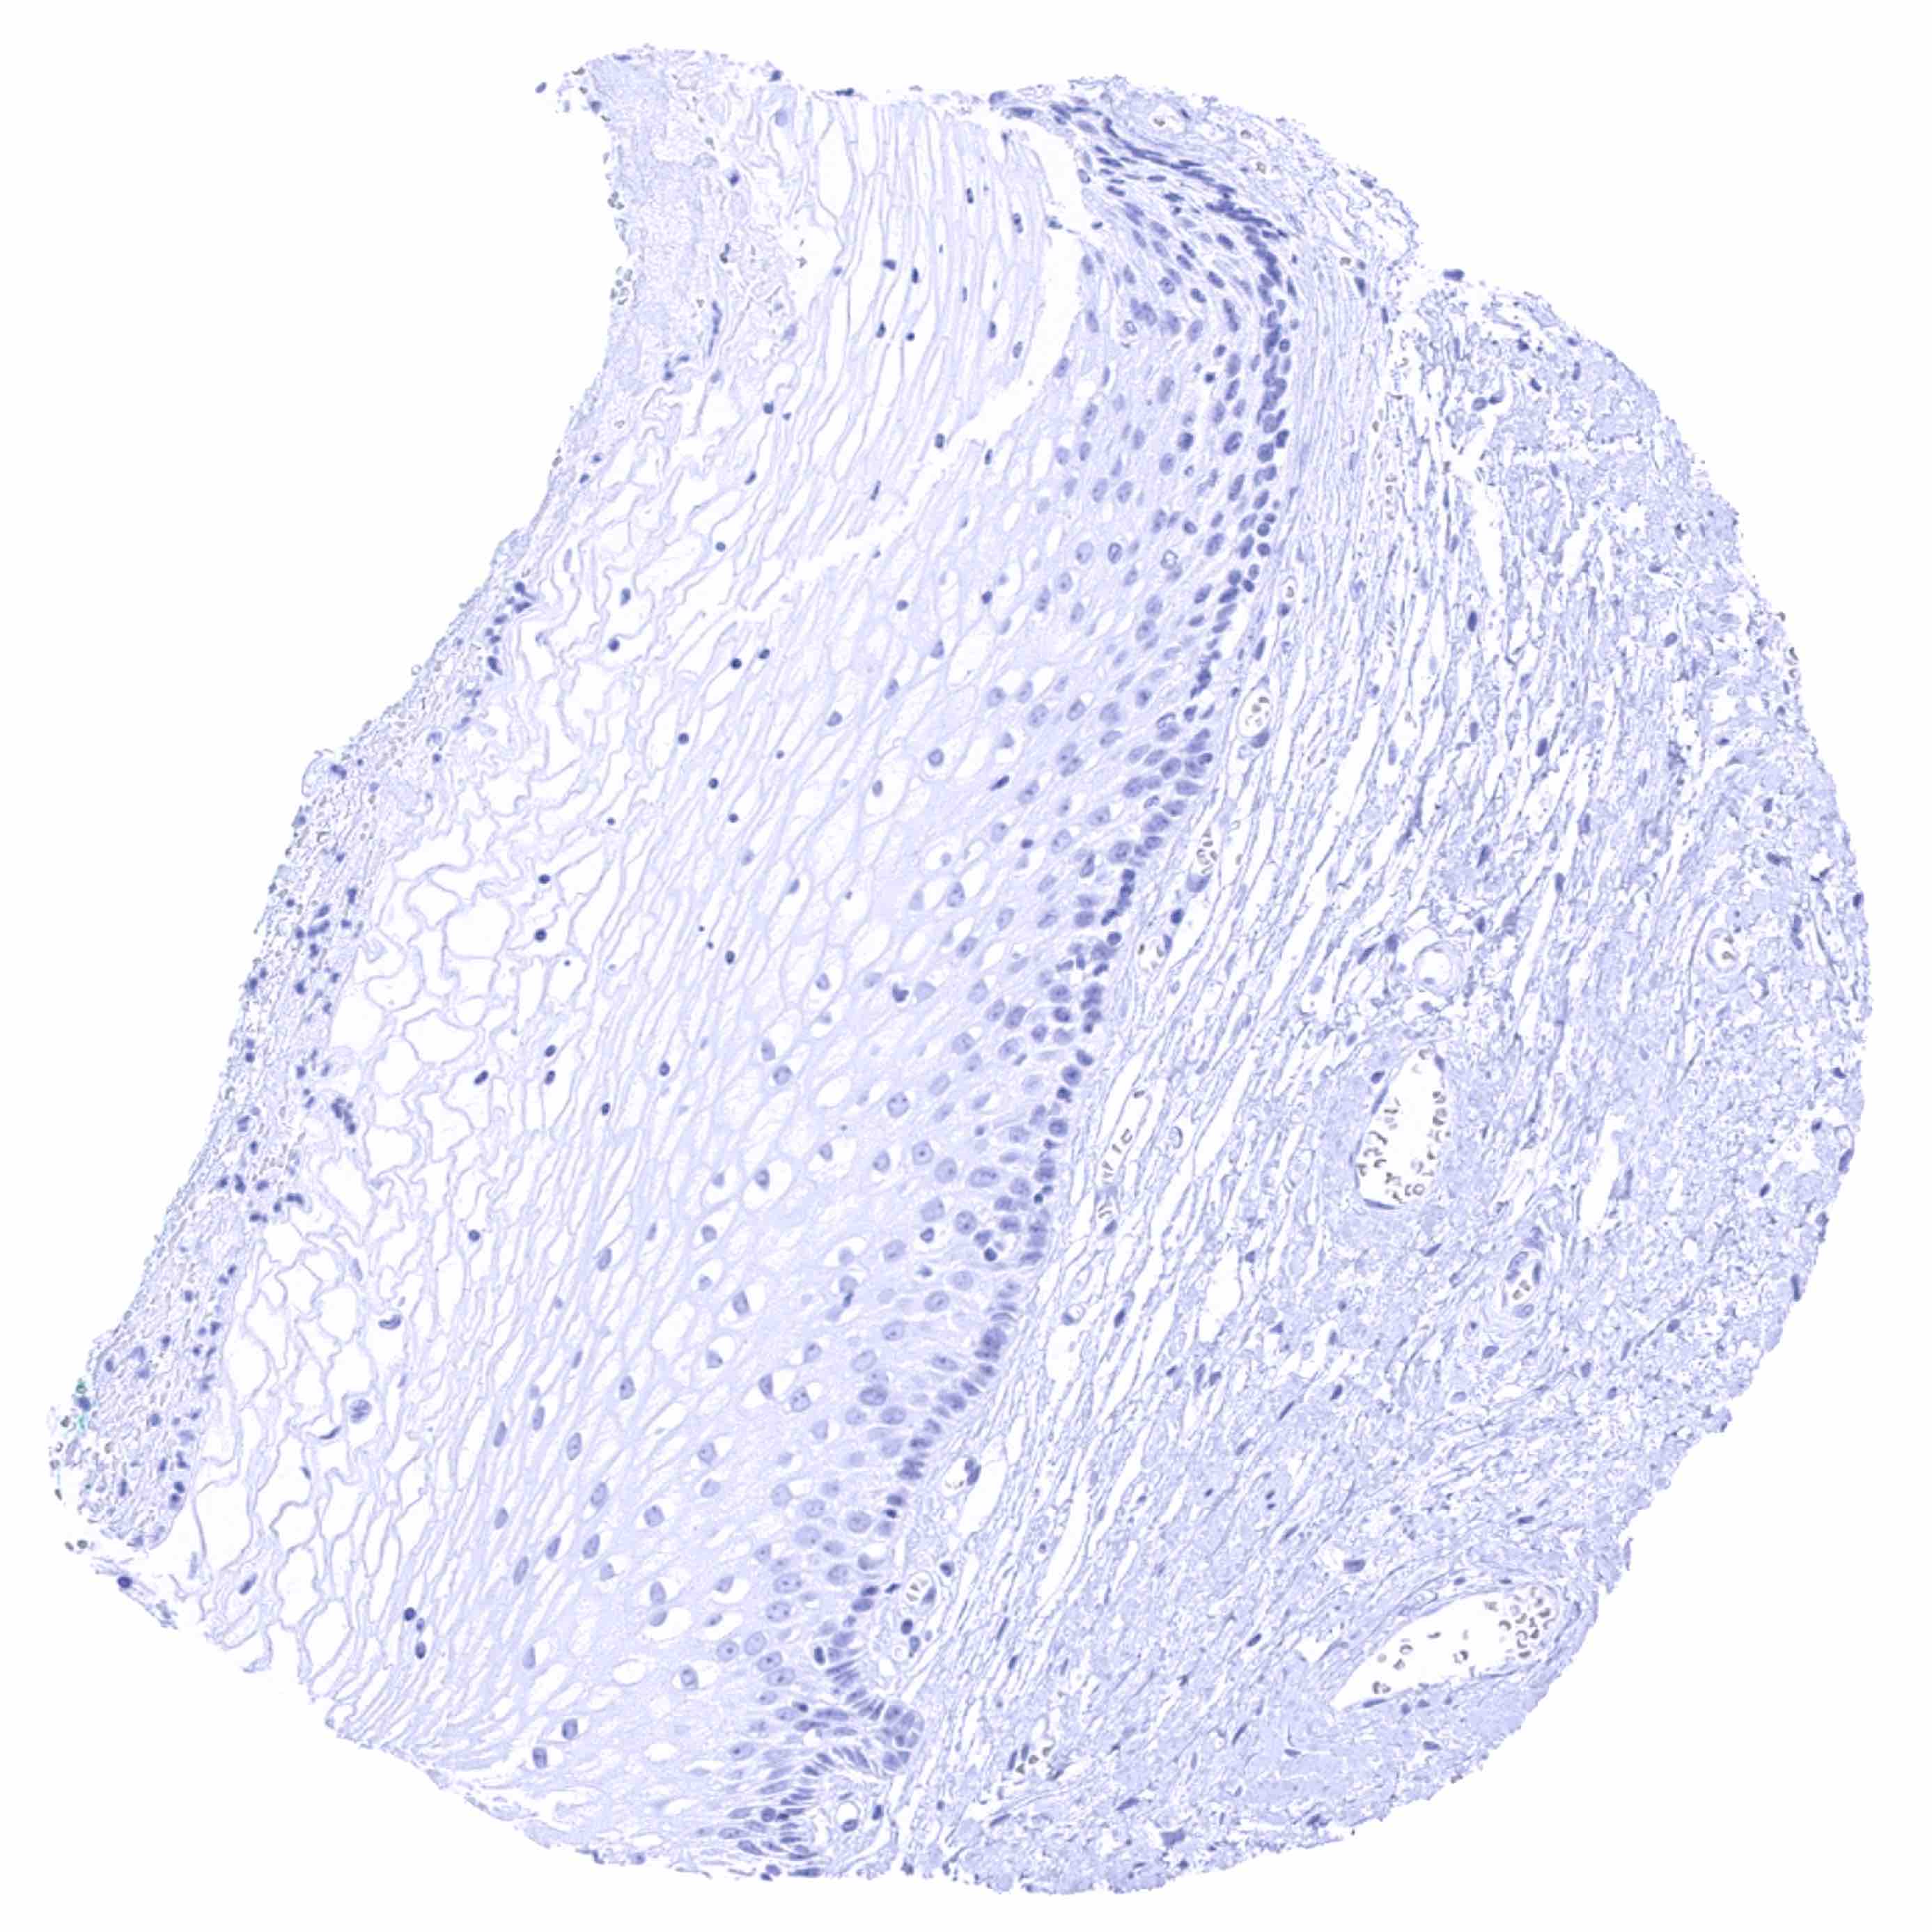

Urinary bladder, urothelium